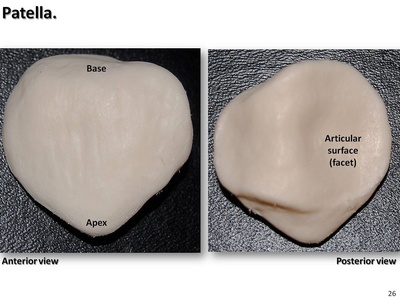

Patella

The patella is the largest sesamoid bone, embedded in the quadriceps tendon over the knee. It acts as a lever to improve knee extension and protects the joint. It’s clinically important for fractures and anterior knee pain.